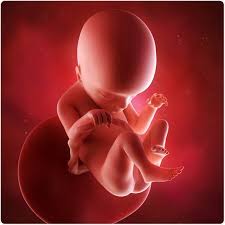

You can see hands, feet, eyes, and ribs. At 17 weeks pregnant, your baby is putting on some fat and gaining muscle. Baby's eyes are opening and she's gaining weight. Total length 17 inches.weight, 3 pounds. This photo shows a baby at 16 weeks of gestation during the second trimester of pregnancy.

Suction aspiration, or vacuum curettage, is the abortion technique used in most first trimester abortions. At this stage, your baby might measure just over five inches long, crown to rump, and weigh about five ounces. The average weight of a baby is about 135 g. When you're 17 weeks pregnant, the fetus is about the size of a pear! What to do in week 17. The baby begins to form a substance called meconium, which is the first bowel movement. Tissues including bones and muscles continue to form. At week 17 the fetus is actively gaining weight and growing.

Pregnancy baby womb baby in womb teratogenicity illustration fetal development week 9 baby unborn pregnant of twins pregnancy week 4 baby in uterus embryo baby womb. I just saw the picture after 3 years and looked up fetal images at 8 weeks and somehow stumbled upon this tragic video. At 15 weeks, roman and other preborn children just need a handful of weeks to grow in their mother's wombs until they reach viability. Suction aspiration, or vacuum curettage, is the abortion technique used in most first trimester abortions. See fetus stock video clips. After meeting while praying on the sidewalk of an abortion facility, edward garcia, a single father of two, and i, a single mother of two, married. And the height is about 12 cm. When life published lennart nilsson's photo essay drama of life before birth in 1965, the issue was so popular that it sold out within days. Miscarried at 13 weeks and 4 days, baby nathan isaiah's short life inside the womb affirms the humanity of the preborn at the earliest stages of life. Baby development at 17 weeks. This photo shows a baby at 16 weeks of gestation during the second trimester of pregnancy. Week 17 of your pregnancy. Our content is doctor approved and evidence based, and our community is moderated, lively, and welcoming.

The baby begins to develop translucent skin. Pregnancy baby womb baby in womb teratogenicity illustration fetal development week 9 baby unborn pregnant of twins pregnancy week 4 baby in uterus embryo baby womb. Mother's powerful photos of baby miscarried at 16 weeks show humanity of preborn children. The size of the fetus at 17 weeks pregnant. Beyond the eighth week of pregnancy, the embryo is called a fetus. Incredible real photos of the human developing in the womb. Length, 10 3/4 inches, crown to rump; This photo shows a baby at 16 weeks of gestation during the second trimester of pregnancy. Suction aspiration, or vacuum curettage, is the abortion technique used in most first trimester abortions. Big bellies at 17 weeks 3 days pregnant. The average weight of a baby is about 135 g. Week 17 of your pregnancy. The mirror reports brooklen nicole spent more than 24 weeks in the womb, but a problem with her placenta.